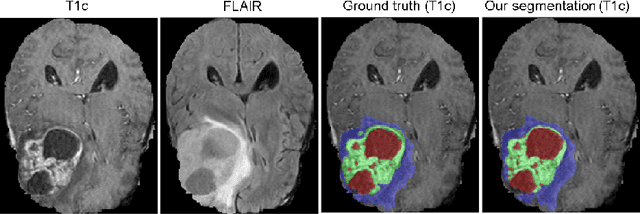

Abstract:Quantitative analysis of brain tumors is critical for clinical decision making. While manual segmentation is tedious, time consuming and subjective, this task is at the same time very challenging to solve for automatic segmentation methods. In this paper we present our most recent effort on developing a robust segmentation algorithm in the form of a convolutional neural network. Our network architecture was inspired by the popular U-Net and has been carefully modified to maximize brain tumor segmentation performance. We use a dice loss function to cope with class imbalances and use extensive data augmentation to successfully prevent overfitting. Our method beats the current state of the art on BraTS 2015, is one of the leading methods on the BraTS 2017 validation set (dice scores of 0.896, 0.797 and 0.732 for whole tumor, tumor core and enhancing tumor, respectively) and achieves very good Dice scores on the test set (0.858 for whole, 0.775 for core and 0.647 for enhancing tumor). We furthermore take part in the survival prediction subchallenge by training an ensemble of a random forest regressor and multilayer perceptrons on shape features describing the tumor subregions. Our approach achieves 52.6% accuracy, a Spearman correlation coefficient of 0.496 and a mean square error of 209607 on the test set.